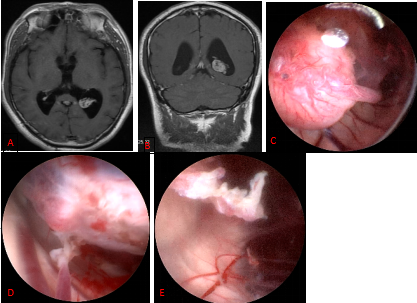

图9. 内镜内技术切除侧脑室脉络丛乳头状瘤A、B:三角区脉络丛乳头状瘤手术前影像;C:术中见肿瘤以及供血动脉;D:电凝供血动脉; E:肿瘤完整全切后。